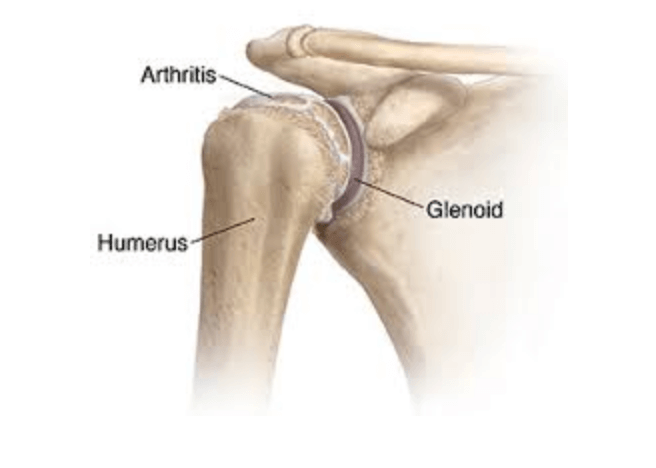

Glenohumeral ligament: анатомия и функции плечевого сустава